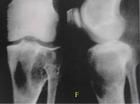

X線顯示病變呈單房性或多房性囊性透亮區,透亮區內可見鈣化斑塊狀陰影。骨皮質內偏心性溶骨性破壞,皮質骨膨脹、變薄,髓腔變窄、邊緣硬化。發生於脛骨時可見前方骨皮質有膨脹性透亮病損,邊緣清晰,很少骨膜反應。少見脛骨多發病變或侵入大部骨幹。